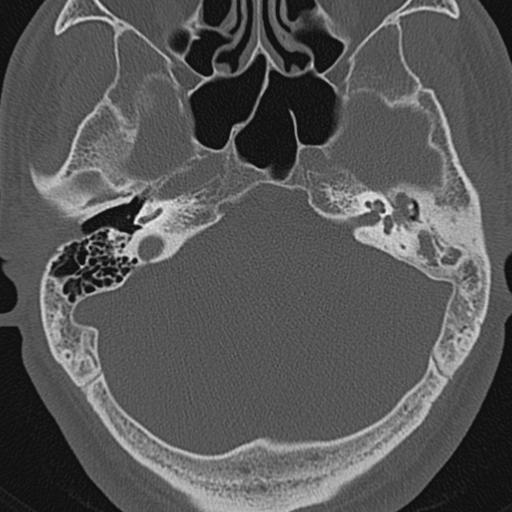

以下是引用zxl51642在2009-8-25 13:37:00的发言:[br]1、左侧慢性硬化型中耳乳突炎(中耳鼓室腔及听小骨受累),并胆脂瘤形成;2、左侧外耳道软组织密度影填塞,考虑炎性肉芽肿,建议结合临床;3、右侧颈静脉窝较左侧明显扩大,不排除颈静脉球瘤,建议mr进一步检查。

以下是引用随光逐影在2009-8-25 19:05:00的发言:[br]1)左侧慢性中耳乳突炎(肉芽肿或胆脂瘤形成),左侧外耳道炎性肉芽肿。2)右侧颈静脉球高位。